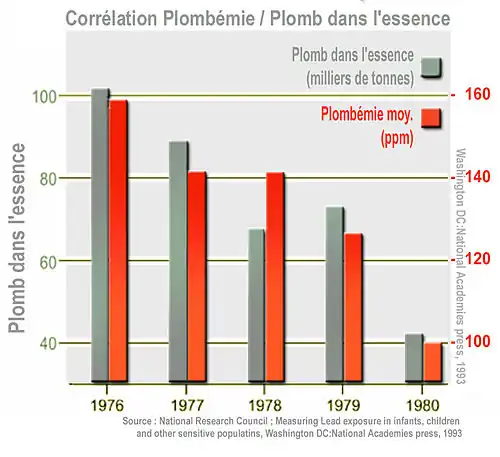

Pendant longtemps, le plomb fut utilisé dans l'essence pour augmenter l'indice d'octane et donc améliorer le fonctionnement du moteur. La combustion de l'essence pouvait alors entraîner des rejets de plombs dans l'air. L'interdiction en France de l'essence plombée (et l'apparition du sans-plomb 95 et 98) en 2000 a pratiquement fait disparaître le plomb de l'air des villes[réf. nécessaire][97],[98].

La plombémie moyenne a nettement décliné dans la décennie qui a suivi l'interdiction du tétra-éthyle de plomb dans l'essence (responsable d'environ 90 % du plomb atmosphérique émis dans l'air de 1923 à 2000[99] avec environ 7 millions de tonnes de plomb ainsi vaporisées dans l'air via les pots d'échappement rien qu'aux États-Unis), mais contrairement à une idée répandue cet additif n'est pas interdit partout, certains grands pays ne l'ayant interdit que tardivement ou ne l'ont pas encore interdit[99] : Nigeria, République du Congo, Arabie saoudite… Le Venezuela ne l'a que récemment interdit, et il y a eu en France des exemptions d'interdiction pour les territoires d'outre-mer.

Une étude postérieure[49], publiée dans le Journal Nature a estimé que ces chiffres élevés étaient dus aux séquelles de la généralisation des additifs plombés de l'essence (il faut environ 20 ans pour que le plomb stocké dans les os soit éliminé), mais que depuis, grâce à une forte chute de la plombémie moyenne dans ce pays, ce facteur de mortalité est à ré-étudier. Les auteurs estiment aussi que les effets du plomb sur la pression artérielle doivent être également réévalués, en lien avec le niveaux actuels d'exposition qui, au moins dans les pays riches, ont considérablement diminué[49].